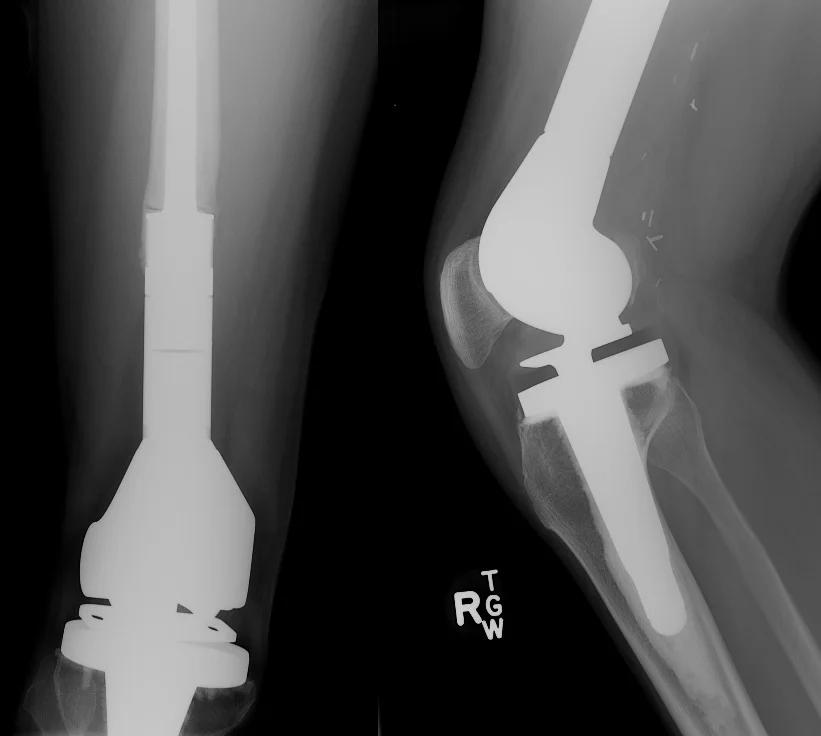

Once the bone is removed, a "trial" implant is assembled to match the size of the removed portion of tibia (first image below). This is tested inside the patient for correct fit. Then, the actual implant is assembled and inserted into the both the femur and tibia (second picture).

When reconstructing the proximal tibia, it is critical that the thigh muscles (quadriceps) are reconnected to the proximal tibia so that the patient can actively extend the knee and walk properly. Since the original tendon connection is removed along with the tibia, we use a portion of the calf muscles ("medial gastrocnemius") to bridge the two areas (third picture below). The final X-ray is shown on the right.